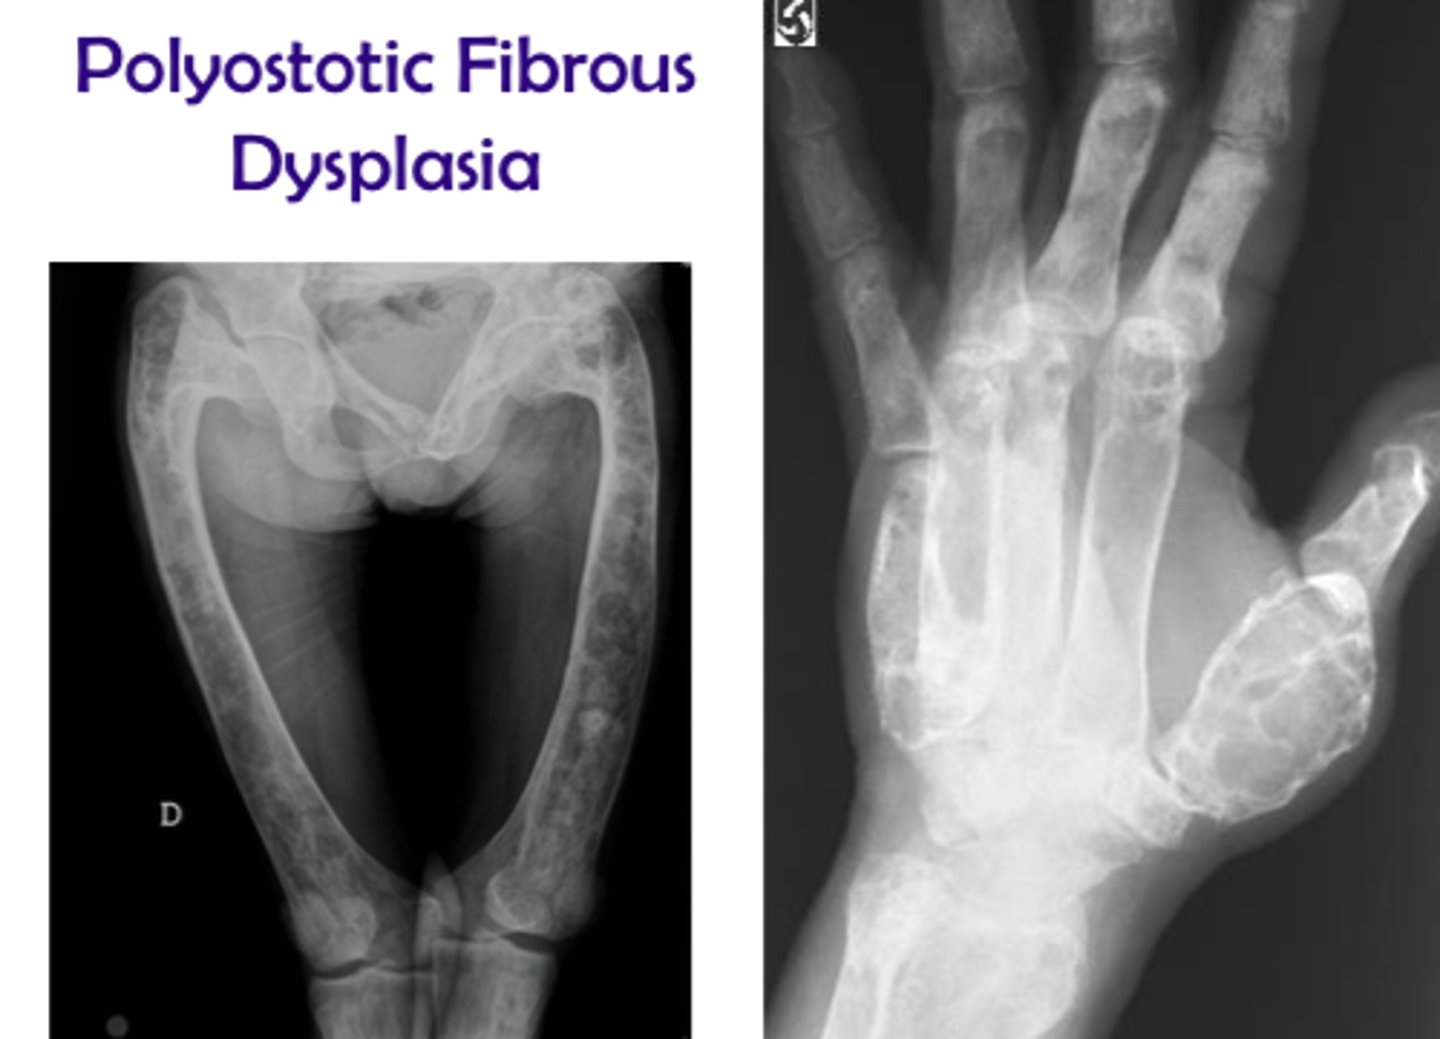

What age group is typically affected by Fibrous Dysplasia?

Young adults

What does Fibrous Dysplasia do to the IAN canal?

Displaces superiorly

What radiographic appearance does Fibrous Dysplasia have?

Ground glass opacity

What is a common clinical feature of Fibrous Dysplasia?

Unilateral facial swelling

When does growth from Fibrous Dysplasia stop?

After adolescence

Are teeth vital in Fibrous Dysplasia?

Yes

Does Fibrous Dysplasia cause pain?

No pain, no symptoms